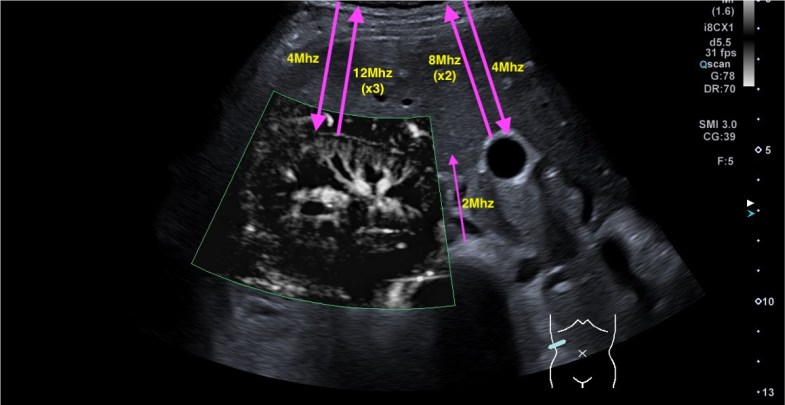

Repasamos anatomía y aprender una forma de estudio de la inserción del tendón del recto anterior del cuadricipital donde vas a ver esas fibras, perfectas. Como se tiene que ver para buscar entensopatías a ese nivel y para que las reconozcas en otras localizaciones típicas, aquiles, epicóndilo…etc…

Lo primero que hice fue tumbar al paciente en la camilla, con una sonda de alta frecuencia posicionada en la zona de dolor, explorando dicha zona en eje largo respecto del fémur, es decir, corte longitudinal.

Encontré esta imagen:

Evidentemente es una imagen patológica comparada con una normal contralateral, la anatomía de la región patológica está cambiada, el hueso está irregular, comparativamente con la zona normal. Esos cambios en el hueso se visualizan en la espina iliaca inferior, donde inserta el tendón del recto anterior, pero este tendón no solo inserta fibras ahí, sino que algunas de ellas insertan justo en la región superior del acetábulo,imagen 3, es decir, justo antes de la inserción en la espina iliaca anteroinferior, algunas se bifurcan hacia profundo, buscando el acetábulo.

Explorar esta zona de inserción es complejo, el recto anterior, que luego es el tendón intramuscular o rafe del recto anterior del cuadriceps, inserta mediante su tendón buscando la profundidad en la cadera, con lo que encontramos anisotropía…te voy a enseñar una forma de explorarlo donde vas a poder corregir esa anisotropía. La exploración habitual es con la pierna en extensión y decúbito supino, pero vamos a pedir al paciente que se siente en la camilla, baje la pierna y apoye el talón del pie, el tronco del paciente mínimamente inclinado hacia atrás, la cadera y la rodilla en extensión y la sonda colocada en la zona de inserción…la imagen que logras es esta maravilla, imagen 3.